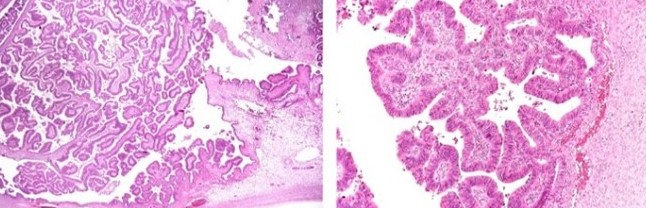

Ιστολογικά ευρήματα βλεννώδους κυσταδενώματος της σκωληκοειδούς. Κυλινδρικό επιθήλιο και παραγωγή βλέννης. Σημειώστε την απουσία ατυπίας και μιτωτικών μορφών